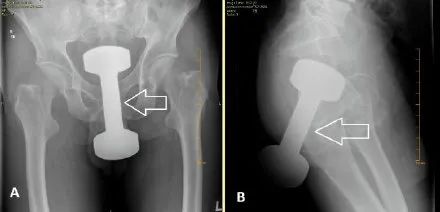

酒瓶、刀、叉子、喷雾罐、哑铃、灯泡、罗非鱼……只有你想不到的,没有“直男”们不敢塞的,比如说,哑铃。

案例一:浙江一小伙在家休息时,将一根20cm长、5cm粗的玻璃棒塞进自己的肛门,无法用手取出后感到肛门胀痛,最后去医院取出。